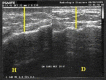

Negative pressure wound therapy (NPWT) is becoming routine for the preparation of wounds prior to grafting for wound closure. We have been using both foam- and gauze-based NPWT to prepare wounds for closure prior to skin grafting and have obtained similar proportions of closed wounds; 7/7 for wounds treated with gauze-based NPWT and 11/11 for wounds treated with foam-based NPWT. In our follow-up consultations we observed that skin grafts on the foam-treated patients were less pliable than those on the gauze-treated patients. To assess what the mechanism of this effect might be, we compared the specific details of the treatments of both 11 foam and 7 gauze patients, including depth, location, patients' age and co-morbidity; biopsies of granulation and scar tissue were taken and stained with haematoxylin-eosin and by Masson's trichrome staining and conducted ultrasound analysis of the closed wounds, to see if there were features which explained those effects. All foam patients were treated at -125 mm Hg for an average of 25·9 days before skin grafts were applied. All gauze patients were treated at -80 mm Hg for an average of 24·7 days before skin grafts were applied. Biopsies of granulation tissue prior to skin grafting from five foam and four gauze-based NPWT patients did not reveal any obvious histological differences between the treatments. Ultrasound analysis of the skin-grafted wounds showed an average depth of scar tissue of 18 mm in the wound beds of the foam-treated wounds and 7 mm in the gauze-treated ones. Biopsies taken on the scar tissue after treatment with the gauze showed a minor tissue thickness and disorganisation and less sclerotic components. The findings of this preliminary analysis suggest that foam-based NPWT may induce a thicker layer of scar tissue beneath skin grafts than gauze-based NPWT which might explain a reduced pliability of the reconstructed bed. At present it is unclear which mechanism might be responsible for the difference in pressure (-125 versus -80 mm Hg), either the length of the time taken to reconstruct the wound bed or the intrinsic nature of the foam or gauze on the tissue surface. Prospective studies are necessary to investigate whether these preliminary observations are confirmed and to investigate what the mechanism might be.